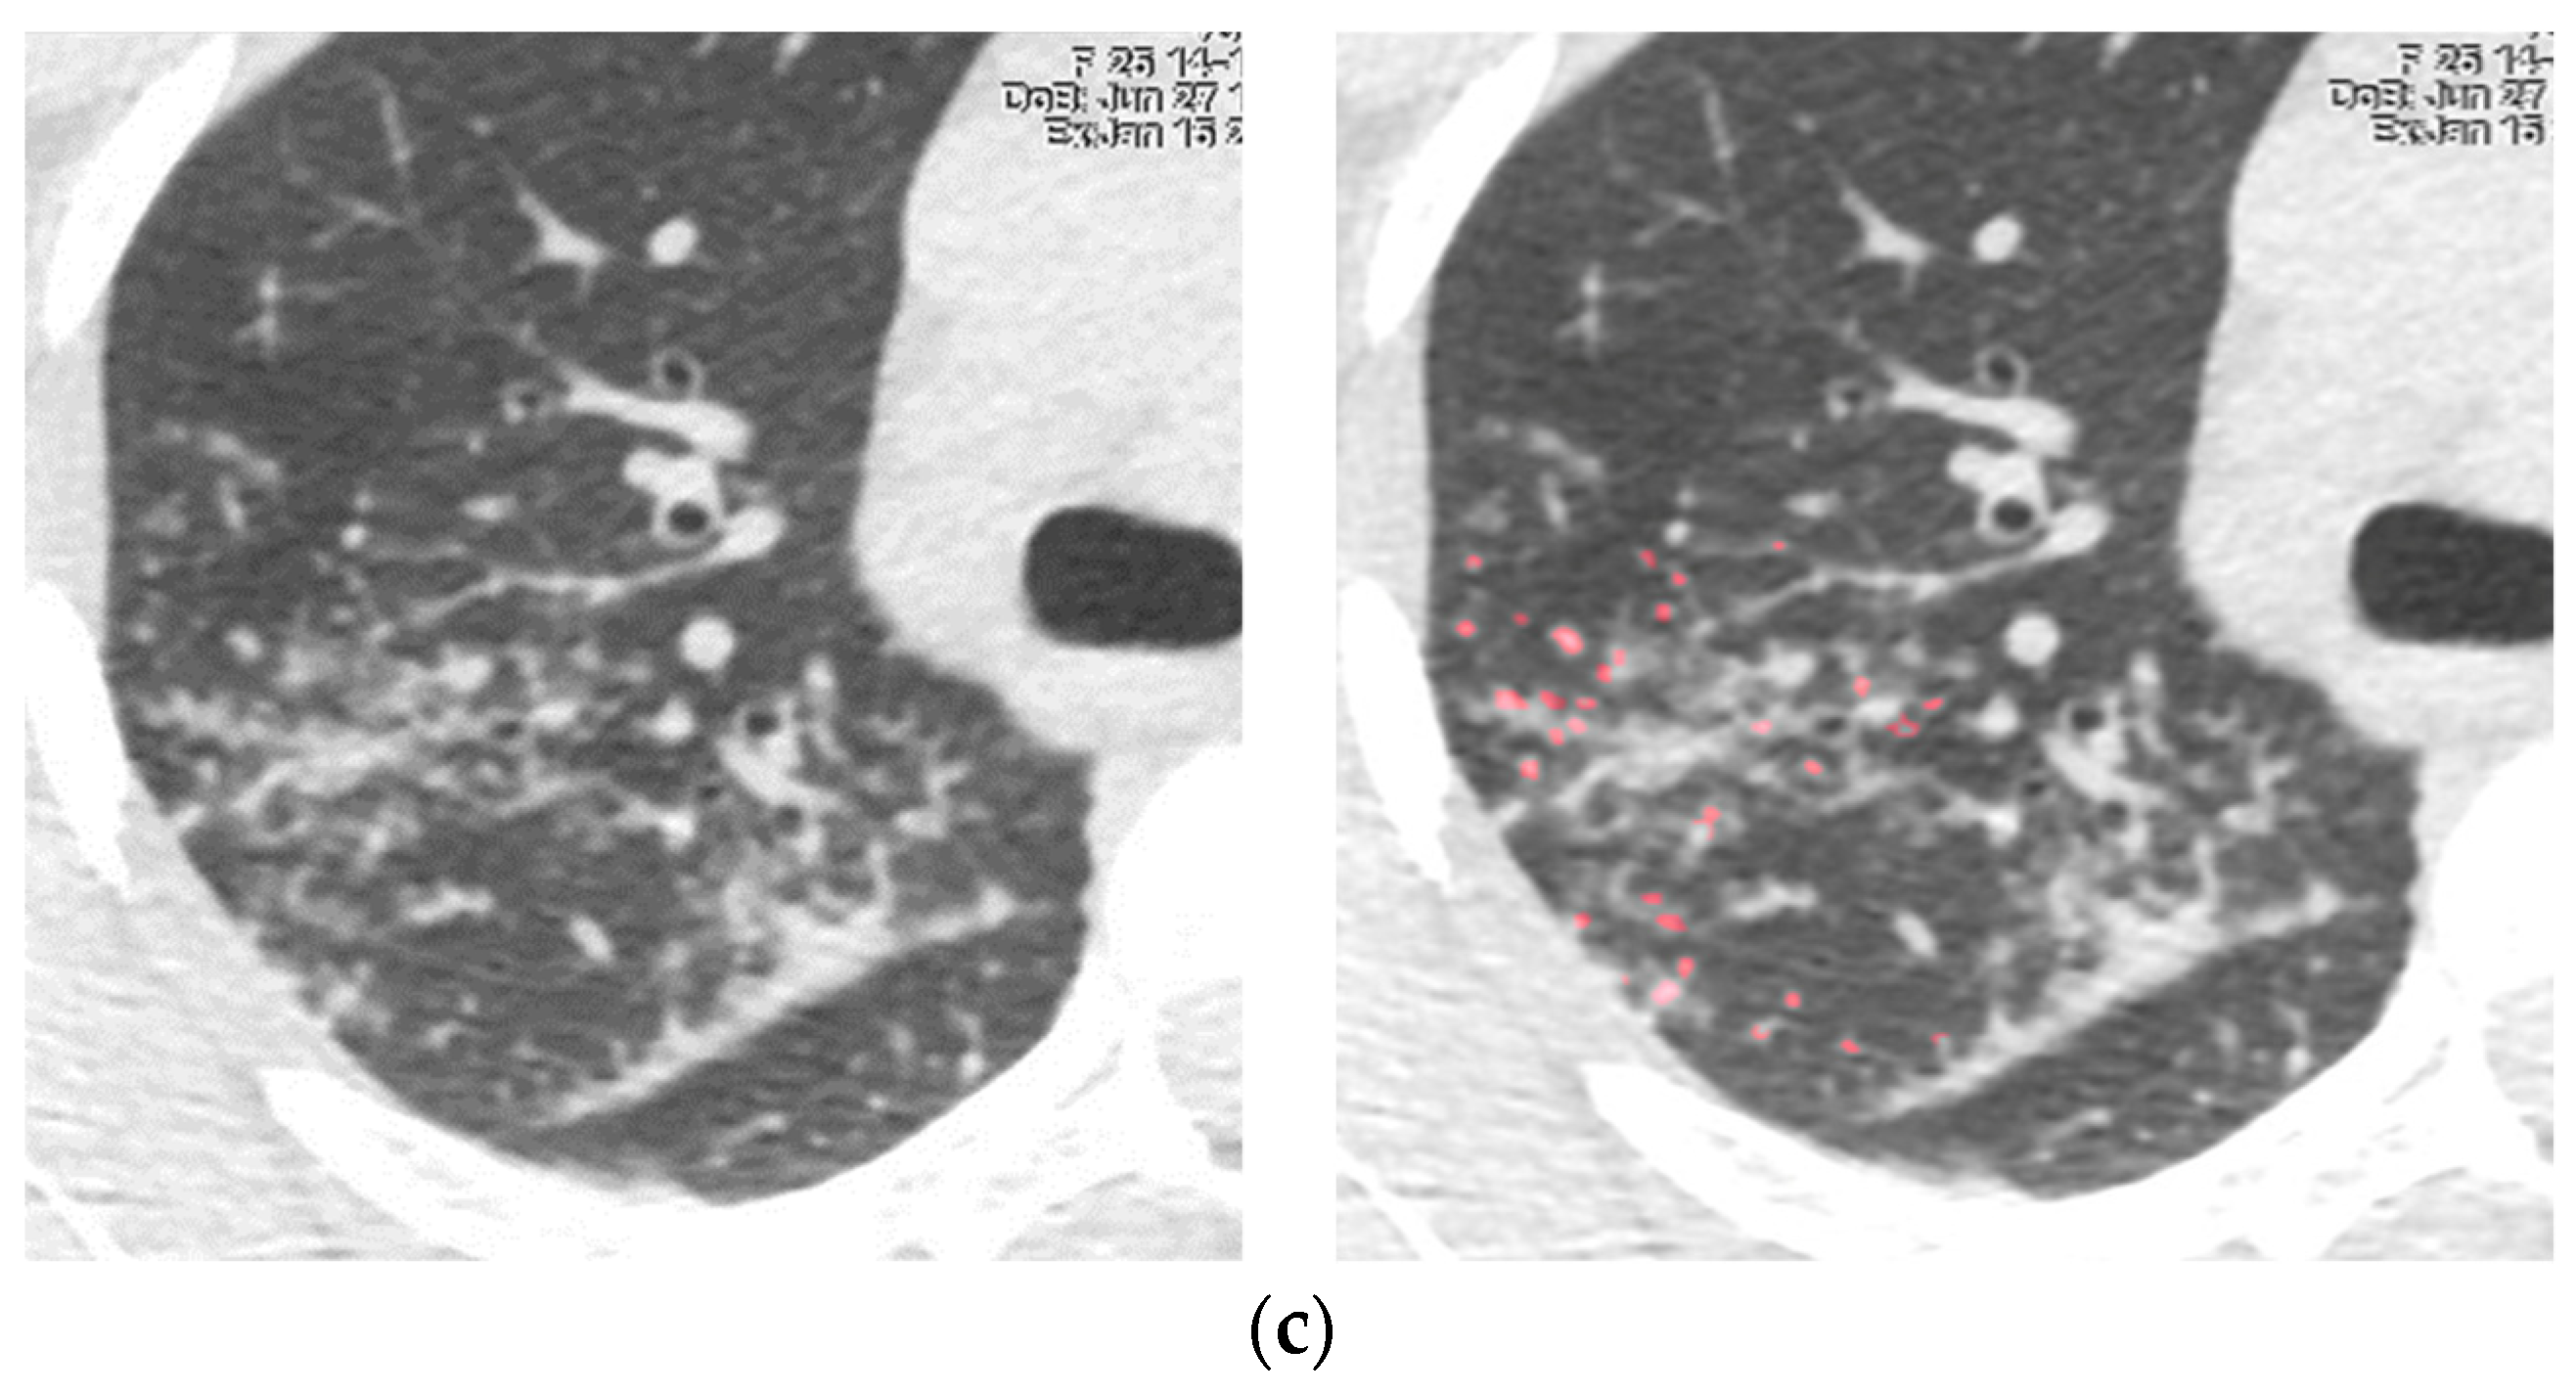

2.2. Follow-Up Testing and Modeling for Predicting the Course of Sarcoidosis

3. Results